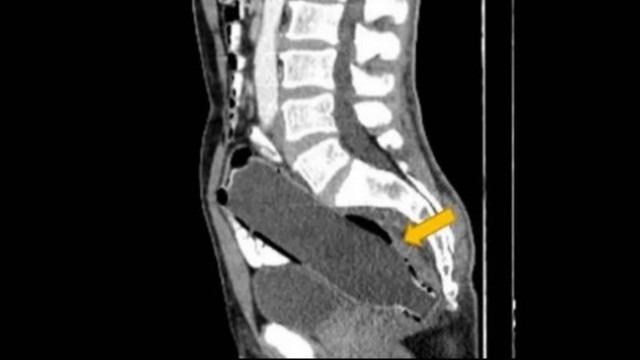

Após uma tomografia computadorizada, a verdade veio à tona: havia uma garrafa de 250ml entalada no seu reto. O fundo da garrafa já estava entrando no intestino grosso, enquanto a boca da garrafa estava a cerca de 10mm da abertura do ânus.